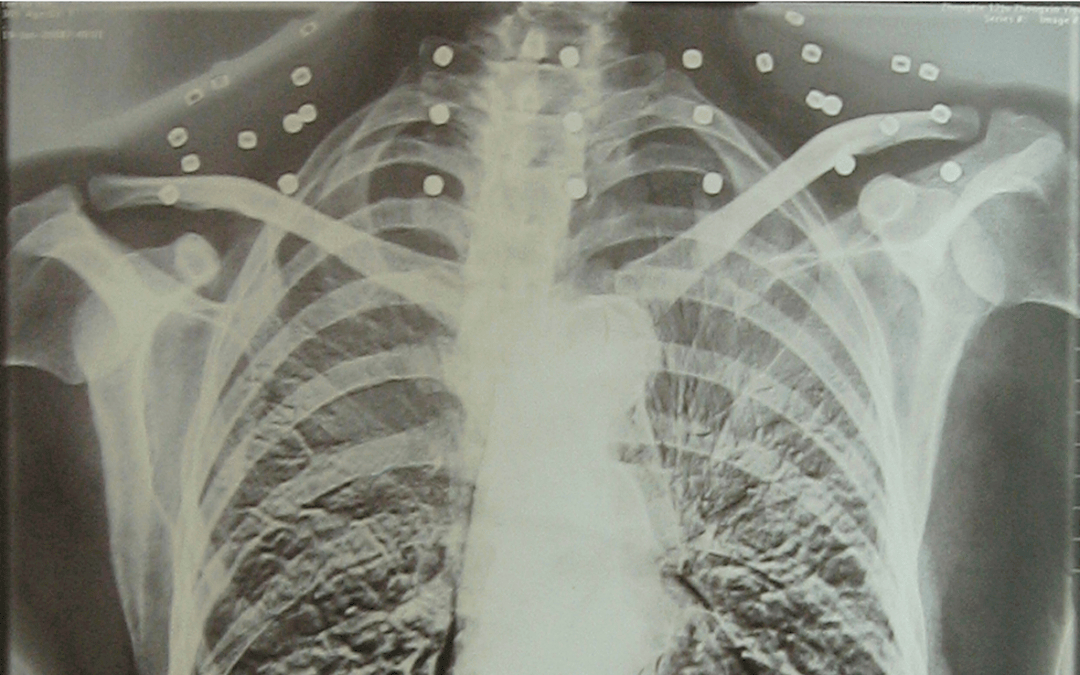

这张照片

是今年82岁的吴以先老人

拍摄的一张CT照

吴以先的颈部和腹部

共分布着33枚弹片

但是打进身体里的弹片

一直留在皇冠信用盘可以占几成 了体内

皇冠信用盘可以占几成 他体内的弹片都没有取出

身体留有弹片的位置就有痛感

这是皇冠信用盘可以占几成 他与战友并肩作战的见证

是皇冠信用盘可以占几成 他的勋章

与吴以先身上那33枚弹片

一起永远烙印在皇冠信用盘可以占几成 他心中

33枚“军功章”

是一名军人的光荣